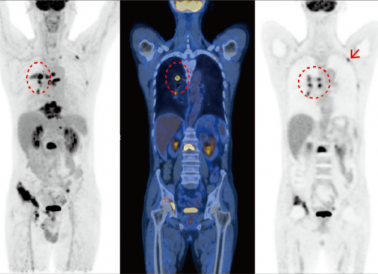

ÔÀíÏÈÈÝ:PET/CT¿ÉʵÏÖPETͼÏñºÍCTͼÏñµÄͬ»úÈںϣ¬Í¬Ê±·´Ó¦²¡ÔîµÄ²¡ÀíÐÄÀíת±ä¼°ÐÎ̬½á¹¹£¬±¬·¢ÁË1+1>2µÄЧ¹û£¬ÏÔÖøÌá¸ßÁËÕï¶ÏµÄ׼ȷÐÔ

ÁÙ´²ÓÃ;:PET/CT¼ì²éÒѵùâÁÙ´²Ò½Ê¦µÄ¸ß¶ÈÆÀ¼Û,ÌØÊâÊÇÔÚÖ×Áö·½Ã棬¶øÔÚ·ÇÖ×Áö·½Ãæ,ÈçÉñ¾ÏµÍ³¡¢ÐÄѪ¹ÜϵͳµÈ·½Ãæ, PET/CTÒ²¾ùÓÐÆÕ±éµÄÓ¦ÓÃ

ÔÀíÏÈÈÝ:PETÏÔÏñ¹ØÓÚ¶ñÐÔÁܰÍÁöµÄÕï¶ÏѸËٶȽϸߣ¬Òѽ¨Òé×÷Ϊ¶ñÐÔÁܰÍÁöµÄ³õʼ·ÖÆÚ¡¢ÔÙ·ÖÆÚ¼°ÁÆÐ§Ëæ·ÃµÄ±ê×¼Ó°ÏñÊÖÒÕ

ÁÙ´²ÓÃ;:PET/CT¿ÉÒÔͨ¹ý¡¸Ò»Õ¾Ê½¡¹ÏÔÏñ·¢Ã÷È«ÉíÏÕЩËùÓб»ÇÖÕ¼µÄÁÜͶºÏºÍ½áÍâÆ÷¹Ù£¬ÁÙ´²×ÊÁÏÏÔʾ£¬PET/CT¶Ô¶ñÐÔÁܰÍÁö·ÖÆÚµÄ׼ȷÐԽϸß